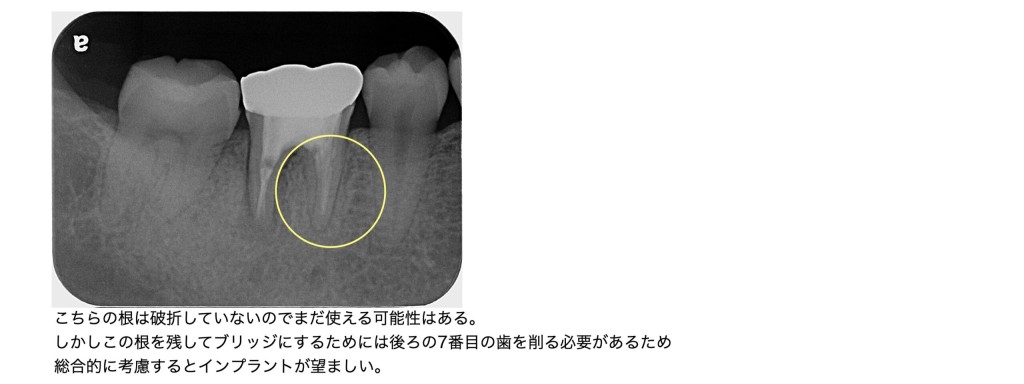

今回、折れていたのは6番の遠心根であり、近心根は残せる可能性がありました。

しかし、

•近心根だけでは土台として弱い

•後ろの健康な7番を削る必要がある

•支台歯の負担が過剰で破折リスクが高い

などの理由から、この状態でブリッジを作るのはナンセンスと言えます。

患者さまの年齢、周囲の歯の状態、治療の持続性を考えると、

今回のケースではインプラントが最も予後が良い選択肢です。